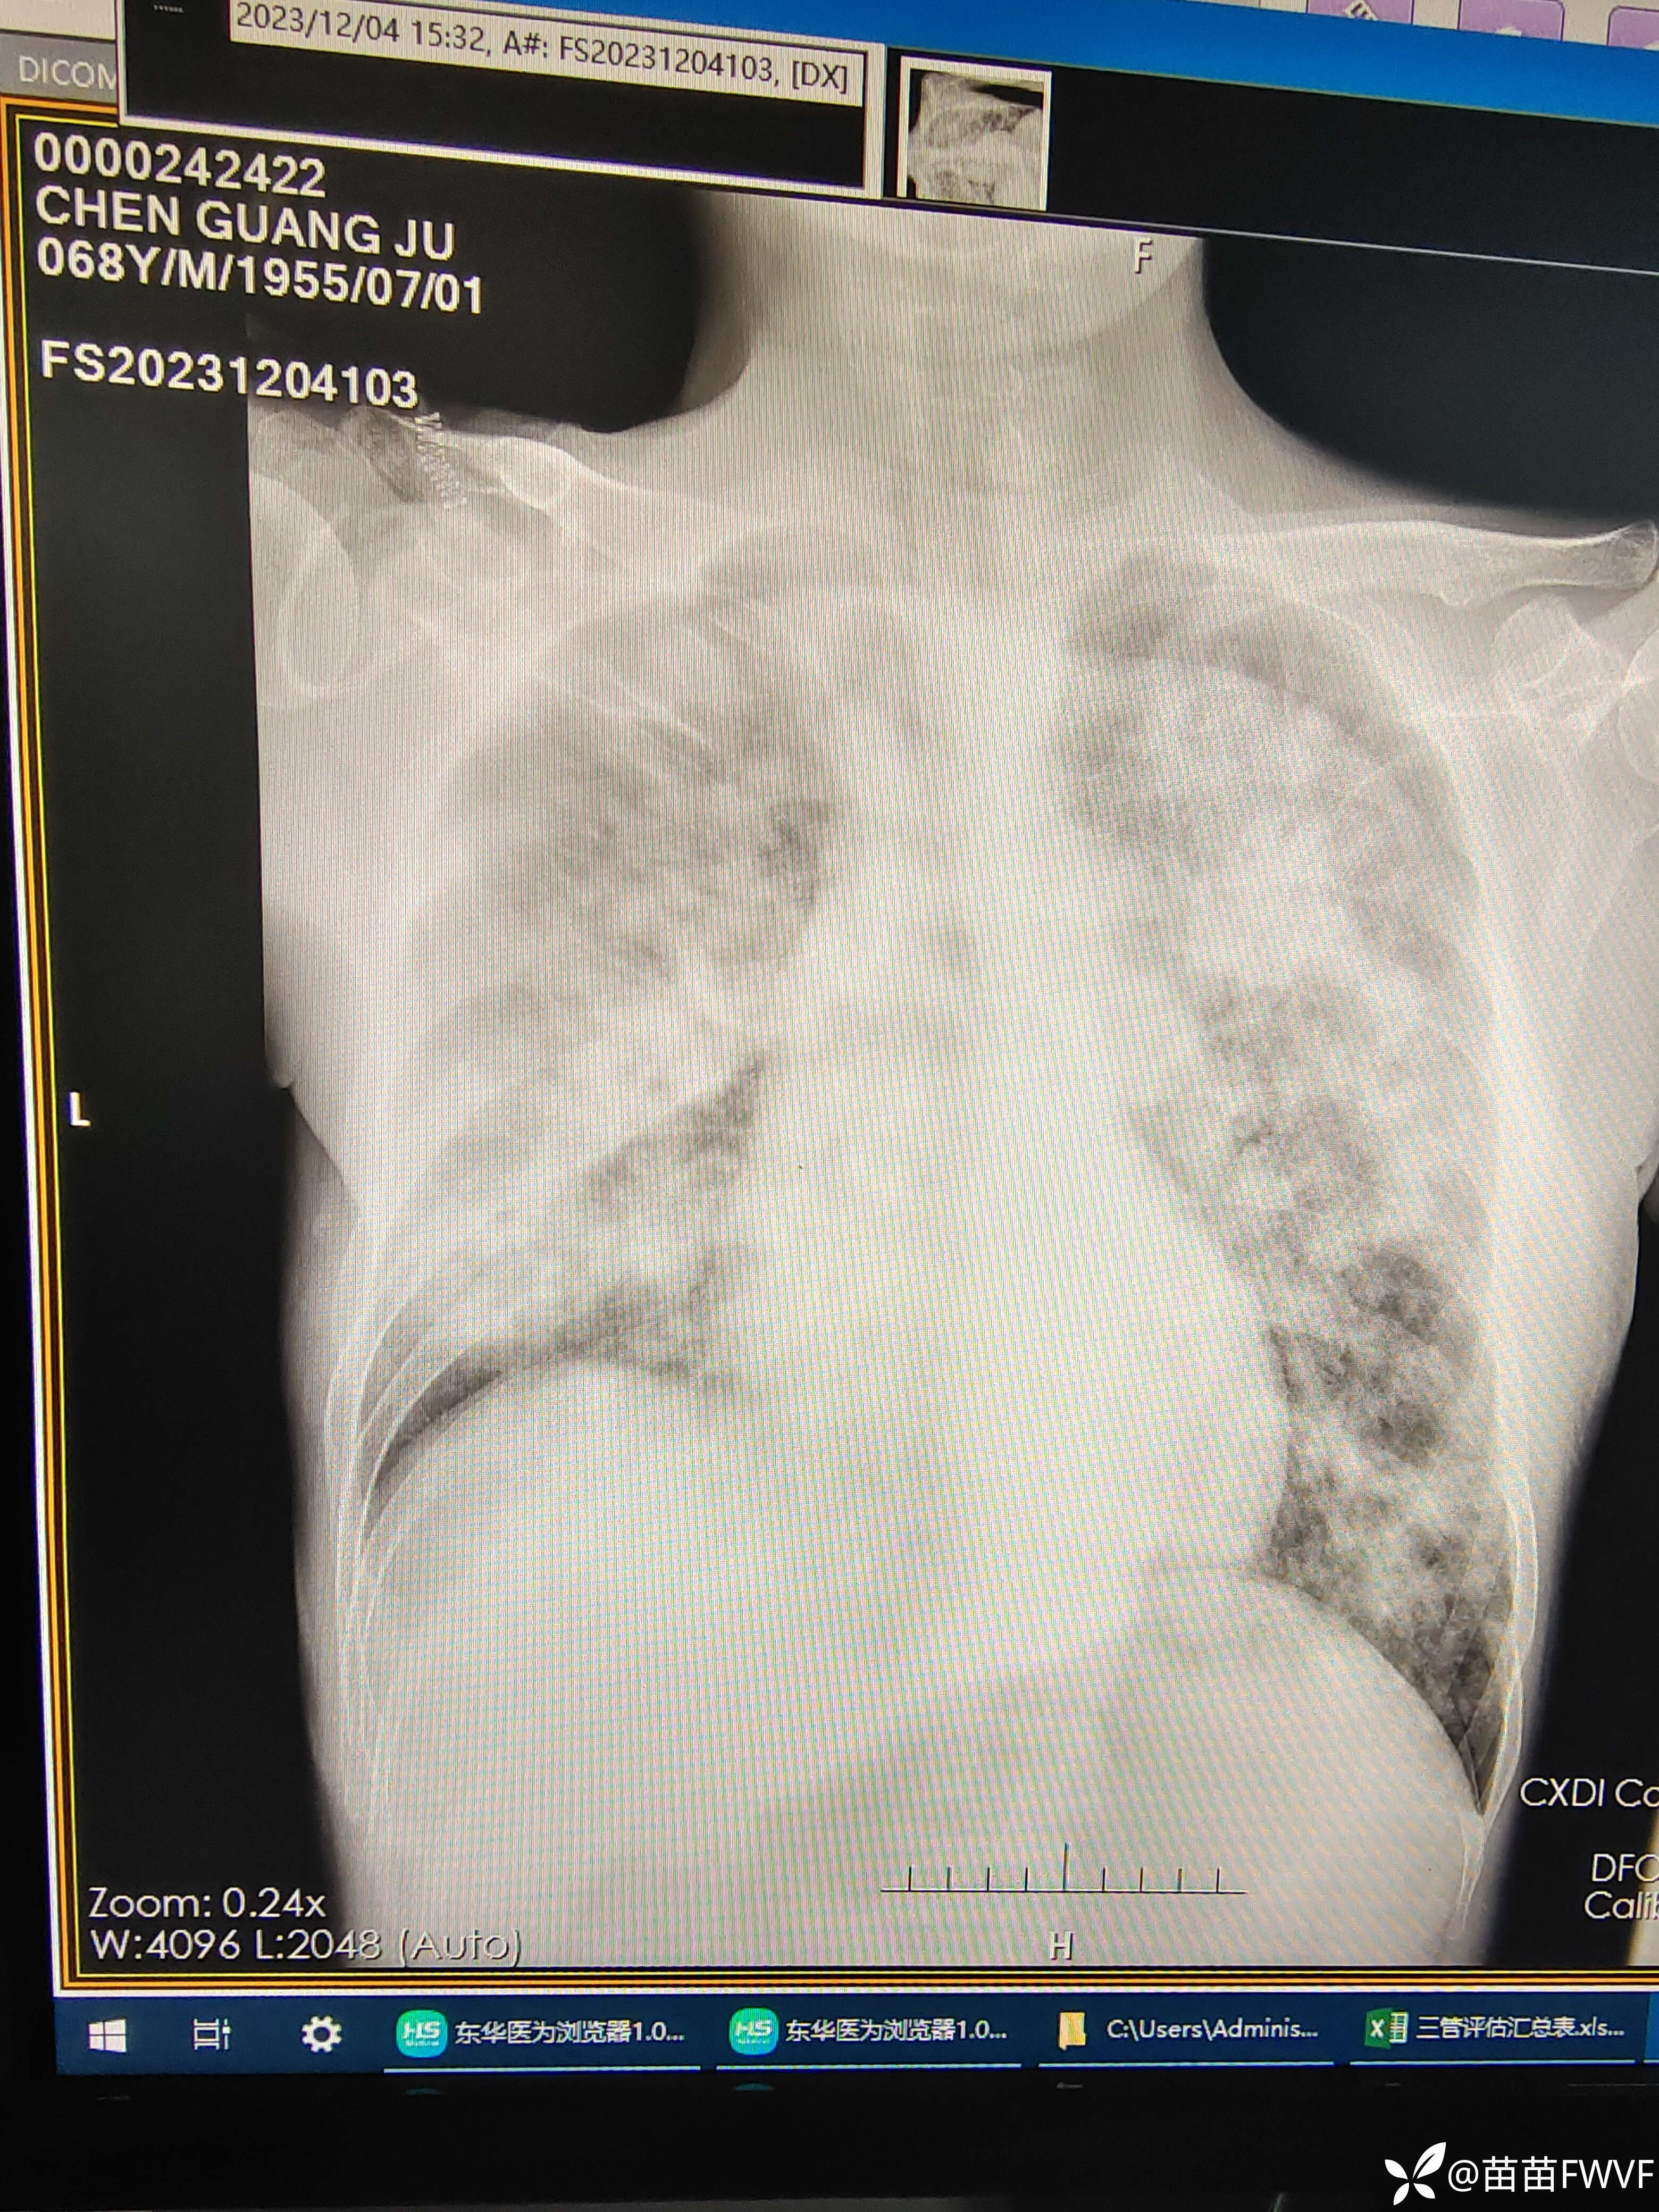

肺部感染加重,完善床旁胸片如下,

img